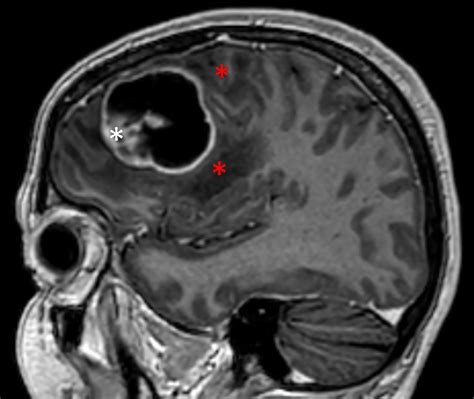

Glioblastoma Multiforme (GBM) is a highly aggressive and malignant brain tumor. It is the most common and deadliest type of primary brain tumor in adults. GBM arises from astrocytes, which are star-shaped cells that make up the supportive tissue of the brain. The tumor is characterized by its rapid growth and invasive nature, making it difficult to treat effectively.

The first step is to diagnose the patient with Glioblastoma Multiforme. This typically involves a combination of imaging studies, such as MRI or CT scans, and a biopsy to confirm the presence of the tumor.